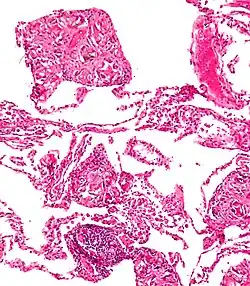

Both children and adults experience problems caused by foreign objects becoming lodged within their bodies. Young children, in particular, are naturally curious and may intentionally put shiny objects, such as coins or button batteries, into their mouths. They also like to insert objects into their ear canals and nostrils.[1] The severity of a foreign body can range from unconcerning to a life-threatening emergency. For example, a coin causes local pressure on the tissue but generally is not a medical emergency to remove. A button battery, which can be a very similar size to a coin, generates hydroxide ions at the anode and causes a chemical burn in two hours.[2] An ingested button battery that is stuck in the esophagus is a medical emergency. In 2009, Avolio Luigi and Martucciello Giuseppe showed that although ingested nonmagnetic foreign bodies are likely to be passed spontaneously without consequence, ingested magnets (magnetic toys) may attract each other through children's intestinal walls and cause severe damage, such as pressure necrosis, perforation, intestinal fistulas, volvulus, and obstruction.[3]